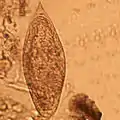

الجسم اسطواني متوسّط طول الذكر 100–150 ميكرو متر بينما الأنثى 120–200 ميكرو متر. جسم الذكر مسطّح له حواف ملتفة للوسط مكوّنة القناة التناسلية أو قناة الاحتضان تُغطّي الأشواك الصفيرة لحافة جسم الذكر الظهرية كما يحتوي الجسم على ممصين (فمي وبطني)من أجل تثبيت الدودة بجدران الأوعية الدمويّة من الداخل يتميّز بيض هذه العائلة بأنّه به أشواك في نهايته أو جانبي البيضة ويوجد داخل الأوعية الدموية الصغيرة ويخرج مع البول أو البراز.